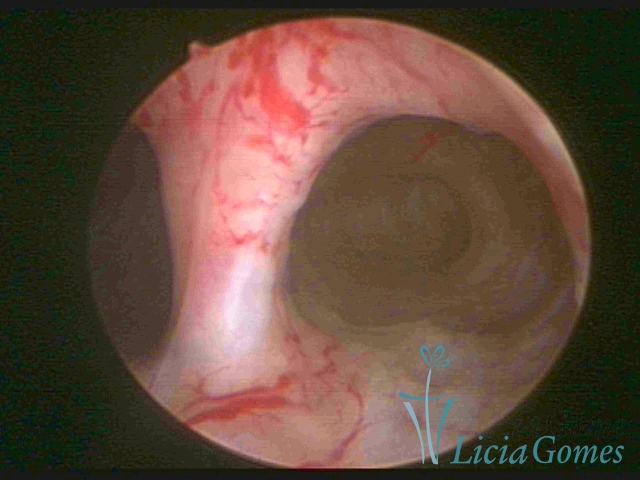

Septate uterus

It probably occurs by the lack of resorption on the middle line, in the merge of Müllerian ducts. The uterus is divided by a partial or total septum which is viewed as a crossbar, not covered by endometrium, which not bleeds when sectioned.

Complete septum when it occupies the whole extension of the cavity, dividing it into two hemicavities.

When this septum occupies only a part of the extension of the uterine cavity, it is considered as incomplete.